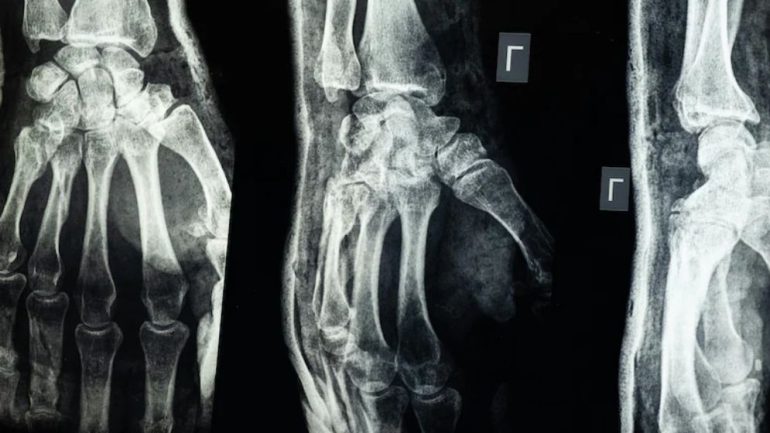

শেয়ার বিজ ডেস্ক : চীনের গবেষকরা দাবি করেছেন, তারা এমন এক ধরনের চিকিৎসা আঠা তৈরি করেছেন যা মাত্র তিন মিনিটেই ভাঙা হাড় জোড়া লাগাতে সক্ষম। নতুন এই ‘বোন গ্লু’ হাড় জোড়ার পাশাপাশি ভাঙা টুকরোগুলোও স্থির রাখতে পারবে এবং হাড় সেরে ওঠার পর এটি শরীরের ভেতর থেকেই স্বাভাবিকভাবে শোষিত হয়ে যাবে। ফলে ইমপ্লান্ট অপসারণের জন্য আরেকটি অস্ত্রোপচারের দরকার পড়বে না।

লিন শিয়ানফেং বলেন, এই আঠা রক্তমাখা পরিবেশেও সঠিকভাবে হাড়কে আটকে রাখতে পারে এবং দুই থেকে তিন মিনিটের মধ্যেই এটি কার্যকর হয়ে যায়। ১৫০ জনের বেশি রোগীর শরীরে সফলভাবে এই আঠা ব্যবহার করা হয়েছে। পরীক্ষায় দেখা গেছে, আঠা দিয়ে জোড়া লাগানো হাড়ের সর্বোচ্চ বন্ধন শক্তি ছিল ৪০০ পাউন্ডের বেশি, শিয়ার স্ট্রেন্থ প্রায় ০.৫ এমপিএ এবং কমপ্রেসিভ স্ট্রেন্থ প্রায় ১০ এমপিএ।

বিশেষজ্ঞরা বলছেন, এই ফলাফল প্রমাণ করে যে ভবিষ্যতে ধাতব প্লেট ও স্ক্রুর মতো প্রচলিত ইমপ্লান্টকে প্রতিস্থাপন করতে পারে এই আঠা। এতে জটিলতা ও সংক্রমণের ঝুঁকিও অনেক কমে যাবে।